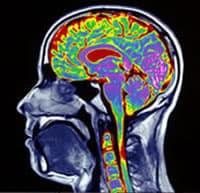

How Much Does a CT Machine Cost?

CT scans are one of the most common practices in the world, yet they are also one of the most costly How much does a CT machine cost and which one is right for you? CT scans are one of the most common practices in … Read more